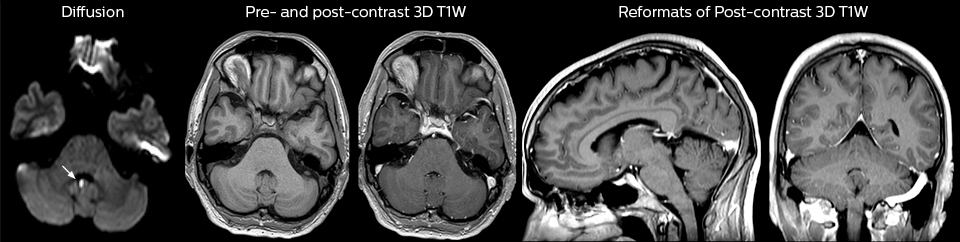

“For the thoracic and cervical spine routine non-contrast exam, for example, we perform one mDIXON T2 TSE sequence, which provides us with two outputs: the fat-and-water-together T2-weighted images, as well as the water-only sagittal T2-weighted images. And then we also perform an axial gradient echo exam.”

Cervical spine routine exam

This patient presented with headache that was worse with neck flexion and we see a Chiari 1 malformation with low-lying cerebellar tonsils as well as some degenerative cervical thrombolytic change.